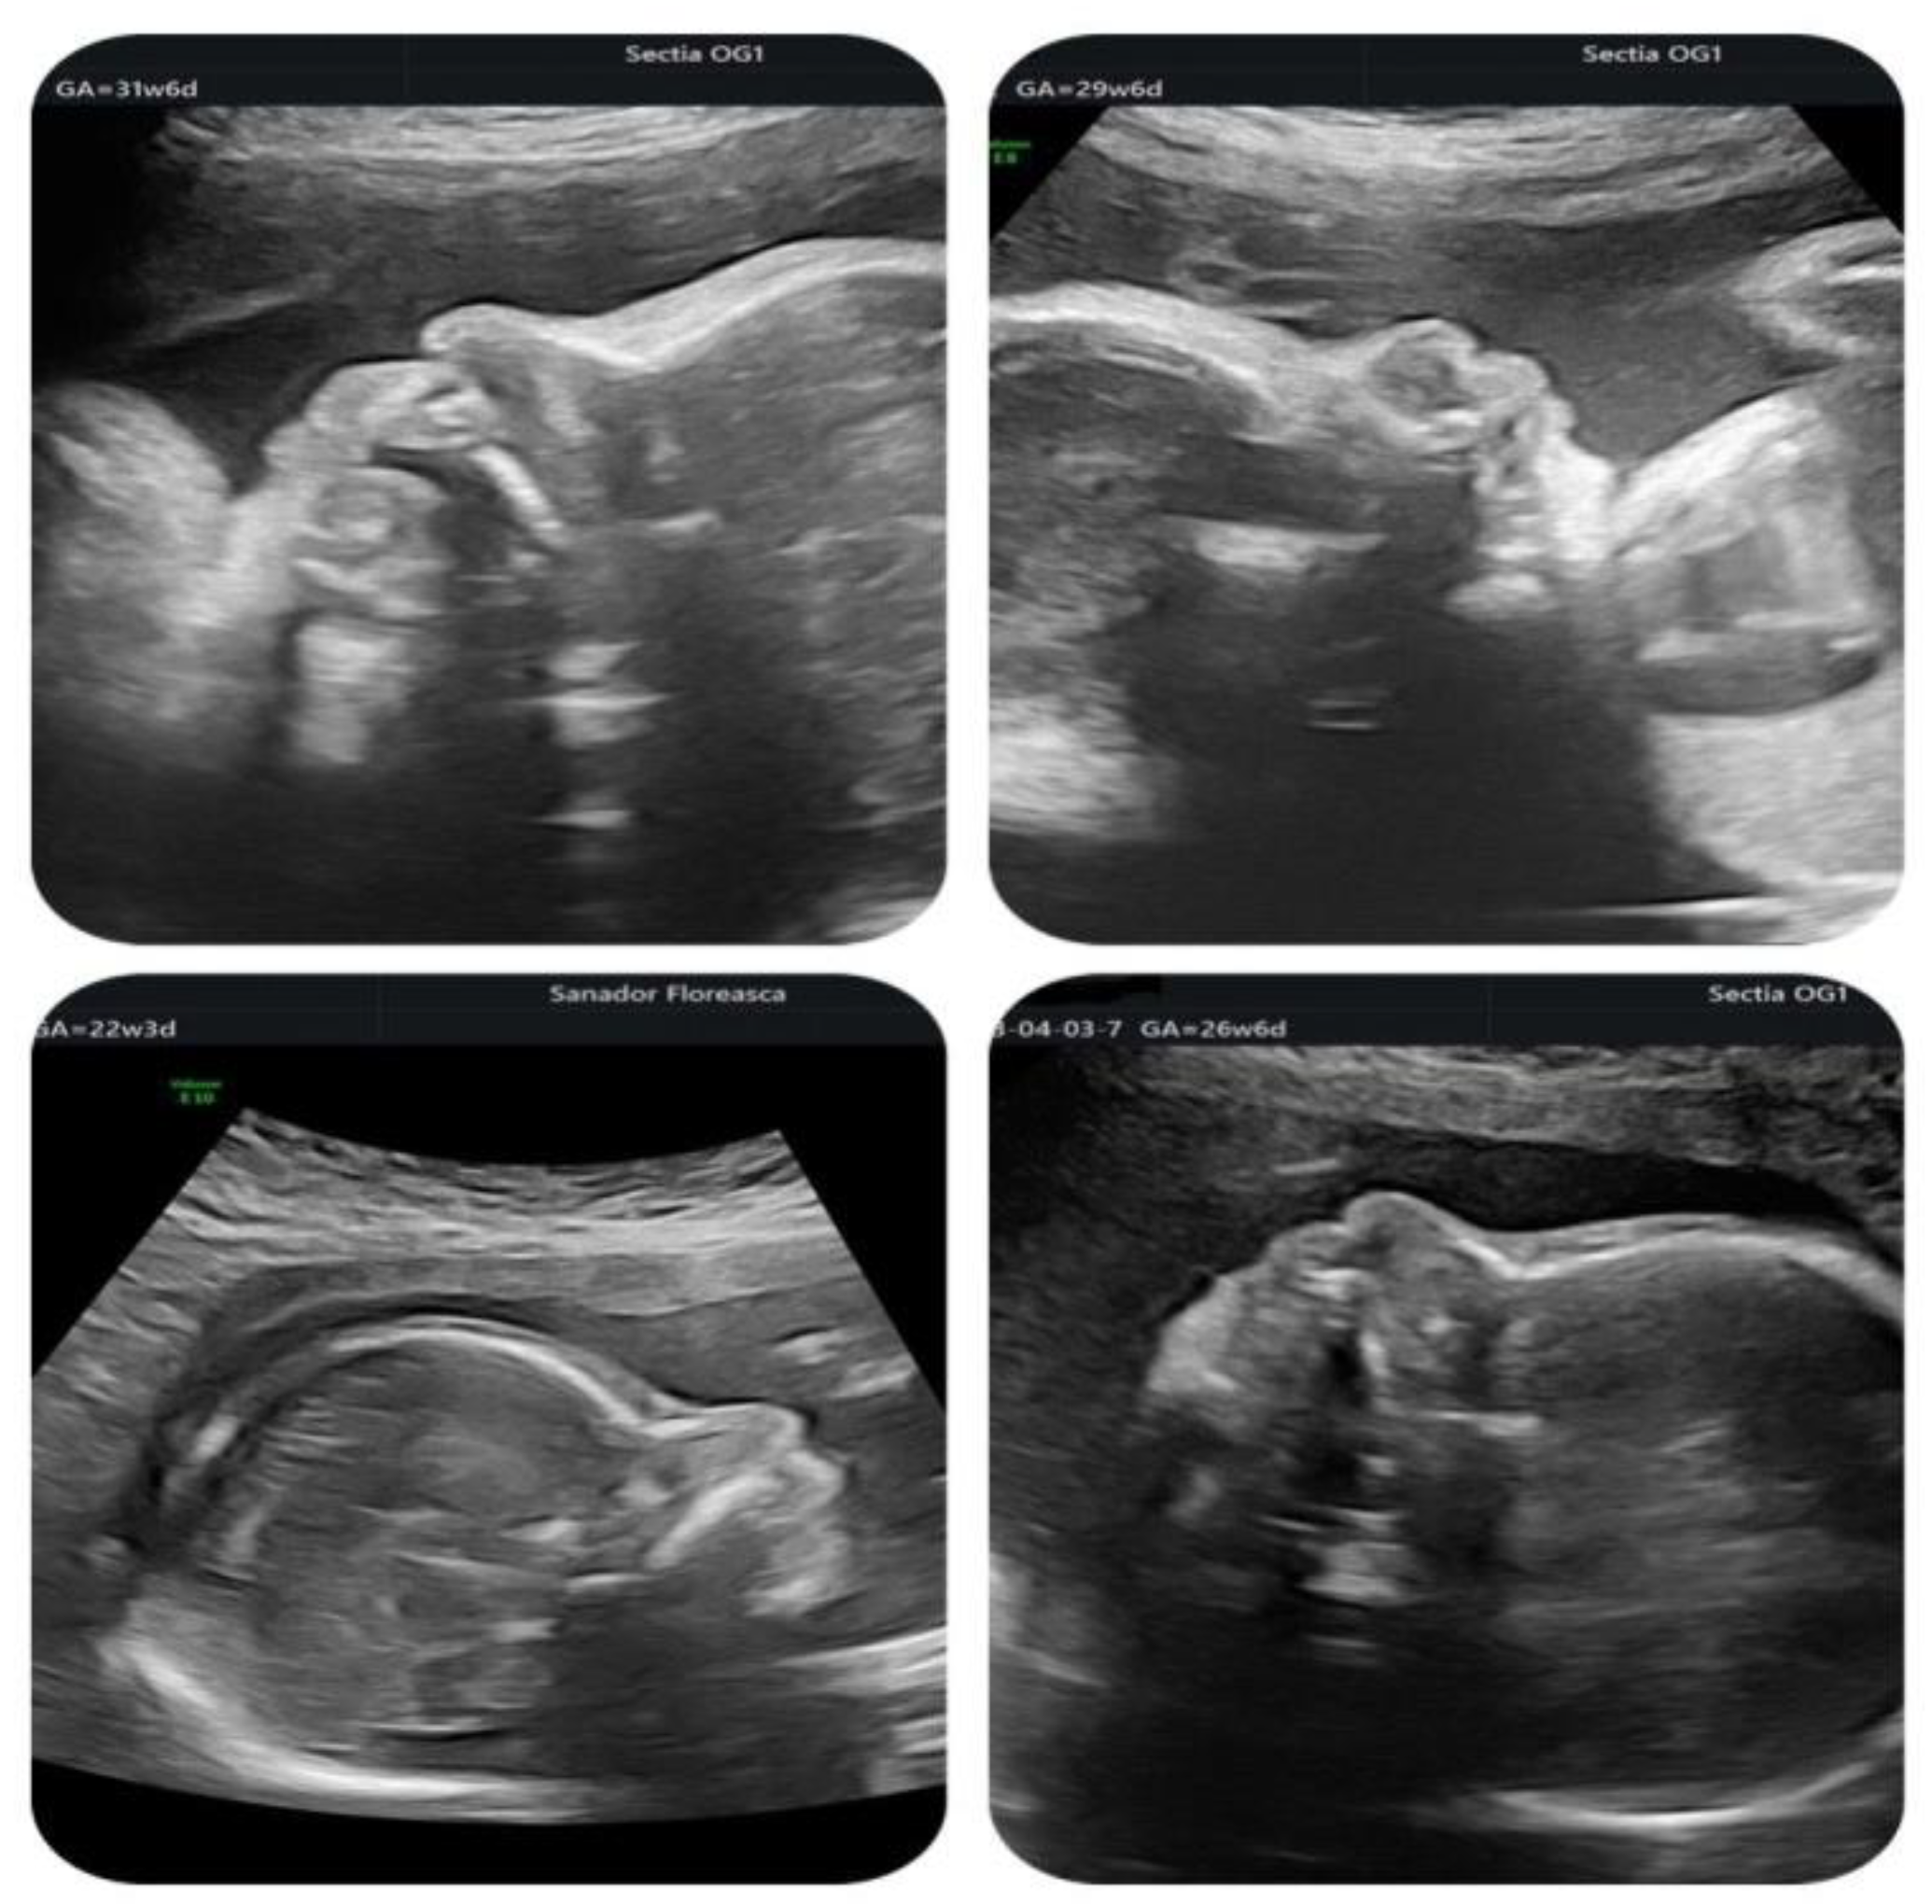

Case Highlights | Details |

---|---|

Maternal age | 34 years |

Gestational age at cardiologic diagnosis | 22 weeks |

Cardiologic diagnosis | IAA type B, malalignment-type VSD, pulmonary valve dyplasia, ARSA |

Genetic diagnosis (amniocentesis with microarray) | 22q11.2 deletion |

Other ultrasonographic findings | Polyhydramnios Enlarged CSP Thymus hypoplasia Bulbous nose |

Delivery route | Vaginal |

Birthweight | 3420 g |

Postnatal echocardiography | Prenatal diagnosis confirmed |

Heart surgery | Performed at 7 days of life Median sternotomy Extended latero-terminal anastomosis of the aortic arch and closure of VSD with bovine pericardial patch, closure of the patent ductus arteriosus Prophylactic antibiotics+ anticoagulants for 10 days |

Total lentgh of stay in the cardiology unit | 3 weeks |

Recommendations at discharge | Sternal precautions for 10 weeks One year prophylactic therapy with ASA + endocarditis prophylaxis |